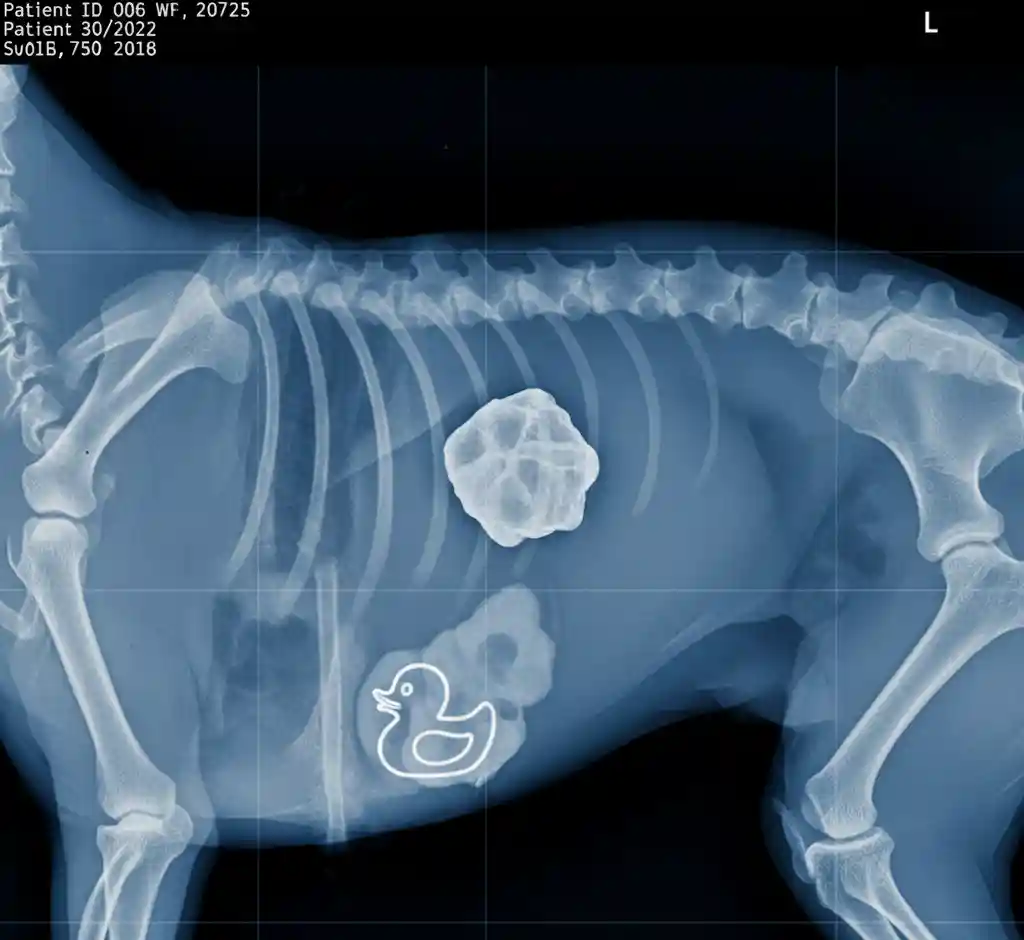

Medical Disclaimer: The information provided in this article is for educational purposes only and does not substitute professional veterinary advice. Always consult your veterinarian if your pet is showing signs of distress. Have you ever heard the phrase, “Better safe than sorry”? It’s never more true than when it comes to your furry friend’s health. […]